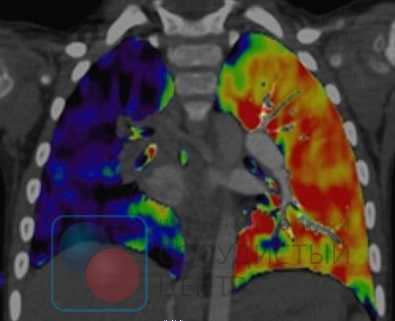

Вентиляционно-перфузионная сцинтиграфия легких является методом скрининга для исключения хронической тромбоэмболии как причины легочной гипертензии. У больных после тромбоэмболии обнаруживаются дефекты перфузии в долевых и сегментарных зонах при отсутствии нарушений вентиляции. Перфузионная сцинтиграфия исторически стала одним из первых методов обнаружения дефектов перфузии легочной паренхимы при ТЭЛА. Изображения, получаемые при острой ТЭЛА и ХТЭЛГ, существенно различаются. Дефекты перфузии при острой ТЭЛА более четко очерчены и резко контрастируют с нормально функционирующей тканью. При ХТЭЛГ дефекты перфузии очерчены не четко и часто не соответствуют зоне кровоснабжения крупной легочной артерии.

Объективным доказательством перенесенной тромбоэмболии легочной артерии (ТЭЛА) становится совпадение по времени клиники тромбоза вен нижних конечностей и появления одышки. В ближайшие месяцы после ТЭЛА у больных можно выявить период, когда состояние остается стабильным и малосимптомным. Это связано с тем, что правый желудочек справляется с нагрузкой и позволяет сохранить хорошую переносимость физических нагрузок до момента развития прогрессирующего ремоделирования легочных сосудов. Практически единственным надежным доказательством перенесенной ТЭЛА могут стать данные перфузионной сцинтиграфии или компьютерной томографии легких, проведенной во время острого эпизода ТЭЛА.